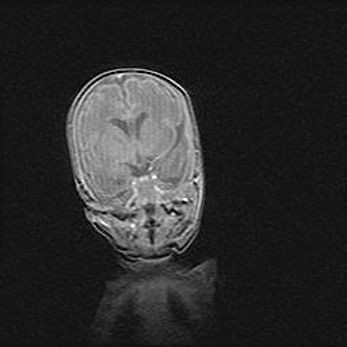

Наружная гидроцефалия с возможной атрофией височных областей.

Возраст: 28 дней

Вес: 3670 г

Пол: мужской

Окружность головы: 38 см

Срок гестации: 40 недель

Гидроцефалия головного мозга у новорожденных – это заболевание, которое характеризуется скоплением избыточного количества спинномозговой жидкости в желудочковой системе головного мозга в результате затруднения её перемещения от места выработки к месту поглощения в кровеносную систему или вследствие нарушения абсорбции. При открытой наружной форме гидроцефалии у новорожденных расширяются и переполняются субарахноидные пространства.

При нормотензивных  формах,  которые,  как  правило,  являются  следствием  перенесенных ишемических  повреждений  паренхимы  мозга,  возможно  сочетание микроцефалии  с нормотензивной гидроцефалией. В основе данных изменений лежит атрофия больших полушарий с преимущественной  локализацией  в  лобно-височных  областях.